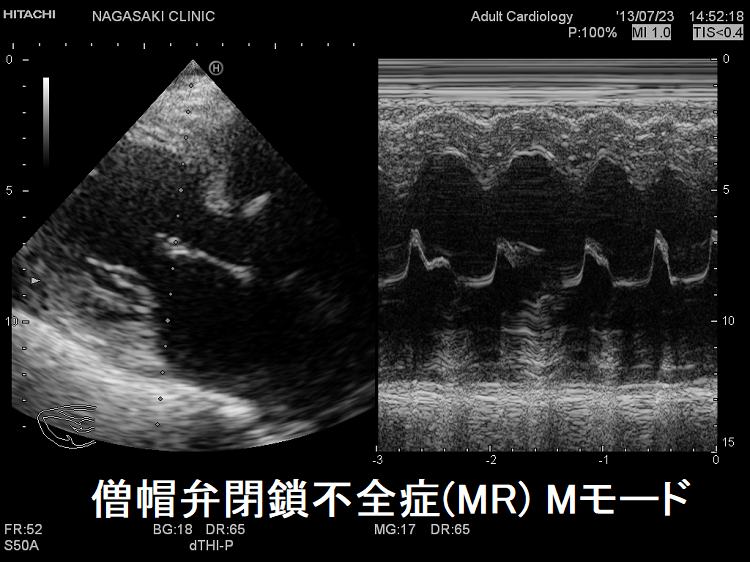

僧帽弁閉鎖不全症(MR)は、

甲状腺機能亢進症/バセドウ病、甲状腺機能低下症/橋本病(下記)

などが原因となります。

甲状腺機能亢進症/バセドウ病、甲状腺機能低下症/橋本病では僧帽弁腱索/乳頭筋断裂の頻度が高い(Endocr Rev. 2005;26(5):704–728.)。

自己免疫性に粘液多糖類が蓄積し、僧帽弁の粘液水腫性変化が生じます

- 甲状腺機能亢進症/バセドウ病の33%

- 甲状腺機能低下症/橋本病の36%

特に循環血液量・心拍出量が増加する甲状腺機能亢進症/バセドウ病では、僧帽弁腱索/乳頭筋断裂を引きおこす危険性が高い。(J Endocr Soc. 2018 Sep 17;2(11):1246-1250.)[Endocrinol Diabetes Metab Case Rep. 2022 Jul 1;2022:22-0298.]

僧帽弁腱索/乳頭筋断裂がなく、粘液腫性変性による中等度から重度の僧帽弁閉鎖不全症(MR)なら、甲状腺機能の正常化に伴い改善する可能性があります。[BMJ Case Rep. 2021 Feb 4;14(2):e239626.]

僧帽弁形成術後に徐脈や心室頻拍(VT)が発生しやすくなります。